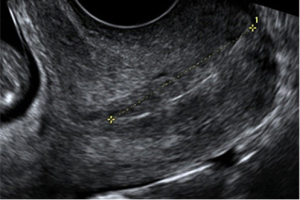

Ecografía Obstétrica Transvaginal

Ecografía Obstétrica Transvaginal Es el método más seguro para evaluar el estado general del embarazo, cuando la gestación no supera las 13 semanas, se debe